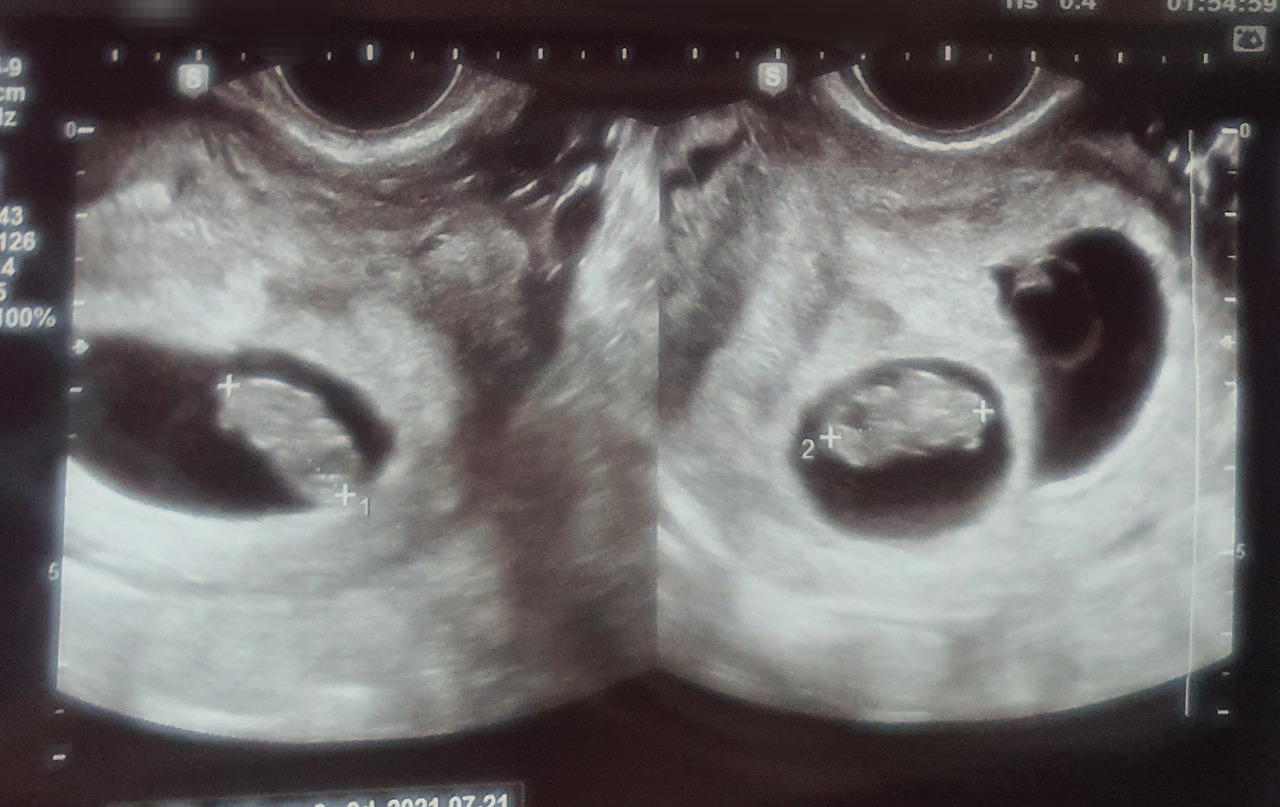

6주 0일.

아기들 심장소리를 듣기 위해 병원으로 갔다. 아기들은 경쟁이라도 하듯 마다의 우렁찬 심장소리를 내게 들려주었다. 심장소리를 처음 듣는 날, 누군가는 감격에 겨워 눈물을 흘린다던데, 나는 그저 담담했다.

8주 0일.

다행히 아이들은 셋 다 열심히 심장소리를 내며 자신들의 존재를 뽐내고 있었다. 크기도 비슷하게 자라고 있었다.

귀여운 젤리곰들